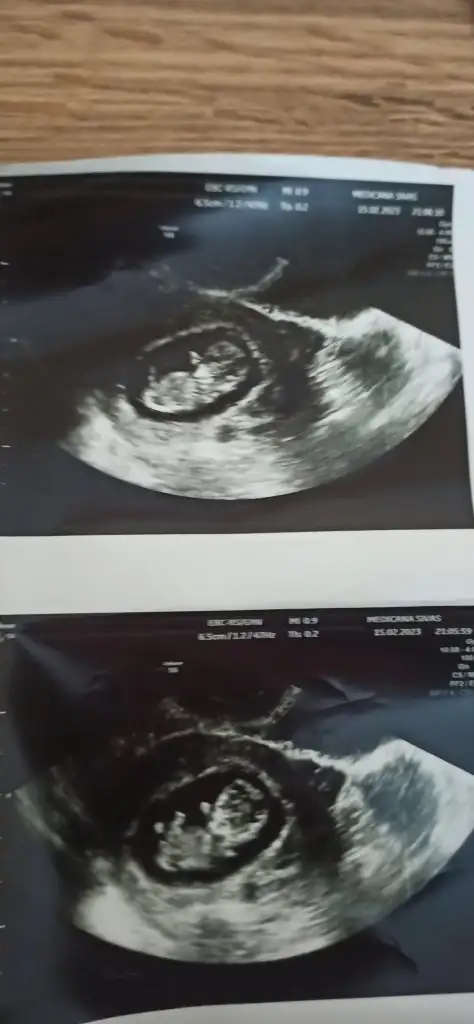

Merhaba kizlar 13+2 deyiz bize de cinsyet tahmini yapabilirmisiniz 🥰

IMG_20230215_223303.webp